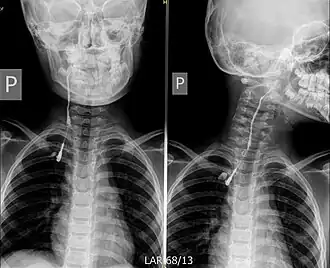

![]() Fistulografía: la flecha amarilla indica el trayecto del contraste que rellena la fístula | ||

La TC y la punción-aspiración con aguja fina (PAAF) son las exploraciones complementarias más útiles. En aquellos supuestos en los que exista una fístula externa, la realización de una fistulografía con contraste resultará conveniente para mostrar el recorrido fistuloso.[6]